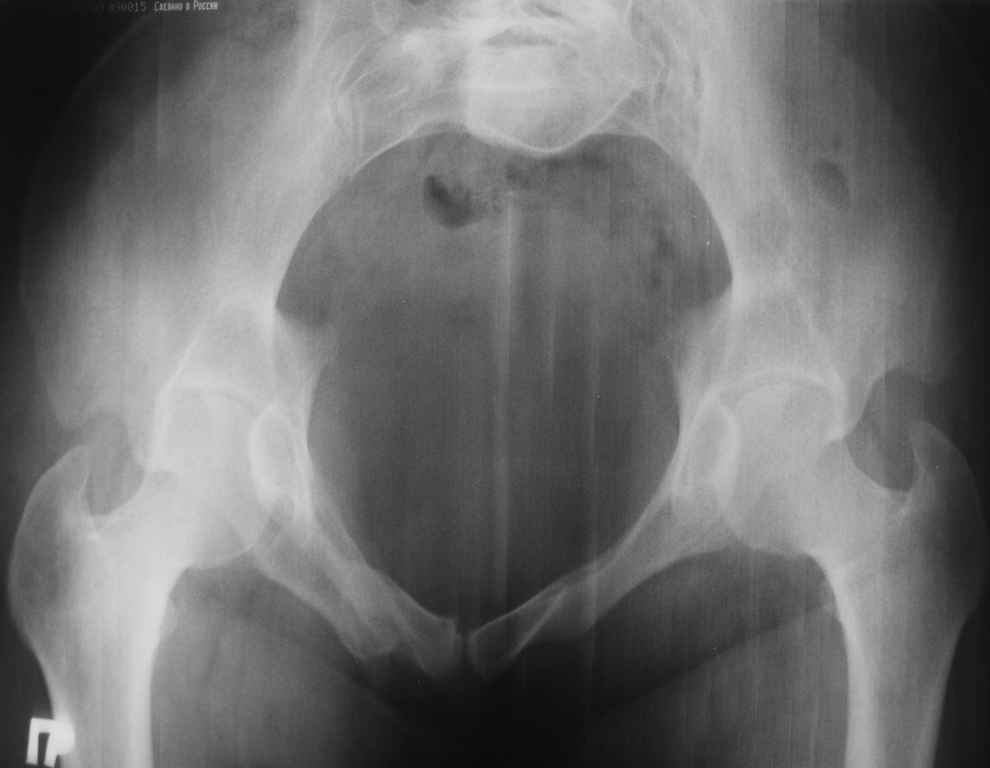

13/03/03 |  13/03/03 |  13/03/03 |  15/09/06 |  15/09/06 |  07/03/07 |  07/03/07 |  19/12/06 | К нам в клинику поступила пациентка 30 лет с диагнозом: Постравматическая ротационная стабильная деформация тазового кольца. Относительное укорочение левой н\конечности на 1 см. Левосторонний компенсаторный сколиоз 2 ст. Болевой синдром. травма автодорожная в январе 2003г. Пассажирка переднего сидения ваз 2109. лечились положением по Волковичу. С марта 2003 года жалуется на боли в тазу, ппояснице усиливающиеся при движении.В настоящее время жалобы на боли в области крестца, КПС больше слева, в пояснично-крестцовом отделе позвоночника. неприятные ощущения, щелчок при выпрямлении правого тазобедренного сустава из положения полного сгибания. боли в тазу появляются при ходьбе ч\з 100 м, так же при вставании из положения сидя, после сидения в течении 2-3 часов. при ходьбе более 100 м появпяется зябкость стоп больше справа. ходит при помощи трости в правой или в левой руке. без трости боли появляются сразу после начала ходьбы. пальпация болезненна в паравертебральных точках средне-грудного и пояснично-крестцового отделов позвоночника, КПС с обеих сторон. Объем движений в тазобедренных суставах полный.правый КПС заблокирован. симптомы натяжения с обеих сторон отрицательны.С 2003г. лечится консервативно, получала ЛФК, массаж, физиолечение - без эффекта. в 2005г. лечилась в санатории с ортопедическим уклоном, получала плавание в минеральной воде, магнитотерапия, массаж, ЛФК. отмечала умеренное улучшение в течении 2 недель.Вопросы:надо ли оперировать, т.е. устранять относительное укорочение левой н\конечности и как?Если не оперировать, то как лечить консервативно?Р-граммы, КТ прилогаются.

Проблема Вашей пациентки находится на границе интересов специальностей ортопедия (вертебралогия) и неврология (нейрохирургия), вероятно, поэтому так мало откликов на ваше обращение. Представленные рентгенограммы не все информативны (особенно спондилограммы от сентября 2006 года). Вероятно, необходимы дополнительные методы исследования к.т. МТГ, ЯМРТ, миелография.

Уважаемый Алексей. Описанные Вами клинические проявления указывают на нестабильность левого крестцово-подвздошного сочленения. Такие больные встречаются не редко (за последние 6мес.в нашей клинике оперировано 3 больных со сроками давности от 6мес. до 1 года). К сожалению рентгенологически их трудно обьективизировать. На КТ это проявляется артрозом и костными разрастаниями КПС. В Вашем случае рентгенограммы и представленные томограммы ничего не дали. Можно попробовать посмотреть связочный аппарат КПС на МРТ хотя не уверен что Вы получите окончательный ответ. Если Вы будете убеждены в этом диагнозе то выход один костно-пластический артродез левого крестцово-подвздошного сочленения с фиксацией канюлированными шурупами. Заманчиво конечно и устранить ротационное смещение половины таза, но это на Ваше усмотрение.

почему она должна возникнуть? Сломан вроде крестец, хотелось бы посмотреть функциональные снимки таза.